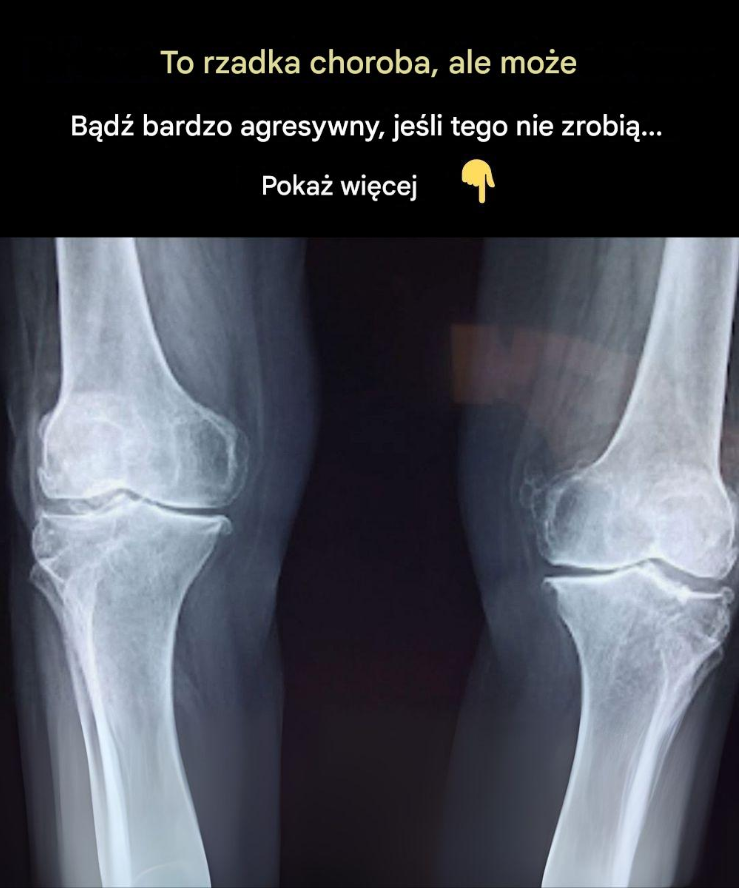

Osteoporoza, często nazywana „cichą chorobą kości”, jest jednym z najczęstszych problemów zdrowotnych wśród osób starszych, zwłaszcza kobiet po menopauzie. Choroba osłabia kości, czyniąc je kruchymi i bardziej podatnymi na złamania. Ponieważ osteoporoza postępuje powoli i początkowo nie daje wyraźnych objawów, wiele osób nie zdaje sobie sprawy z choroby, dopóki nie dojdzie do złamania kości. Rozpoznanie wczesnych objawów i podjęcie działań profilaktycznych ma kluczowe znaczenie dla zdrowia kości.